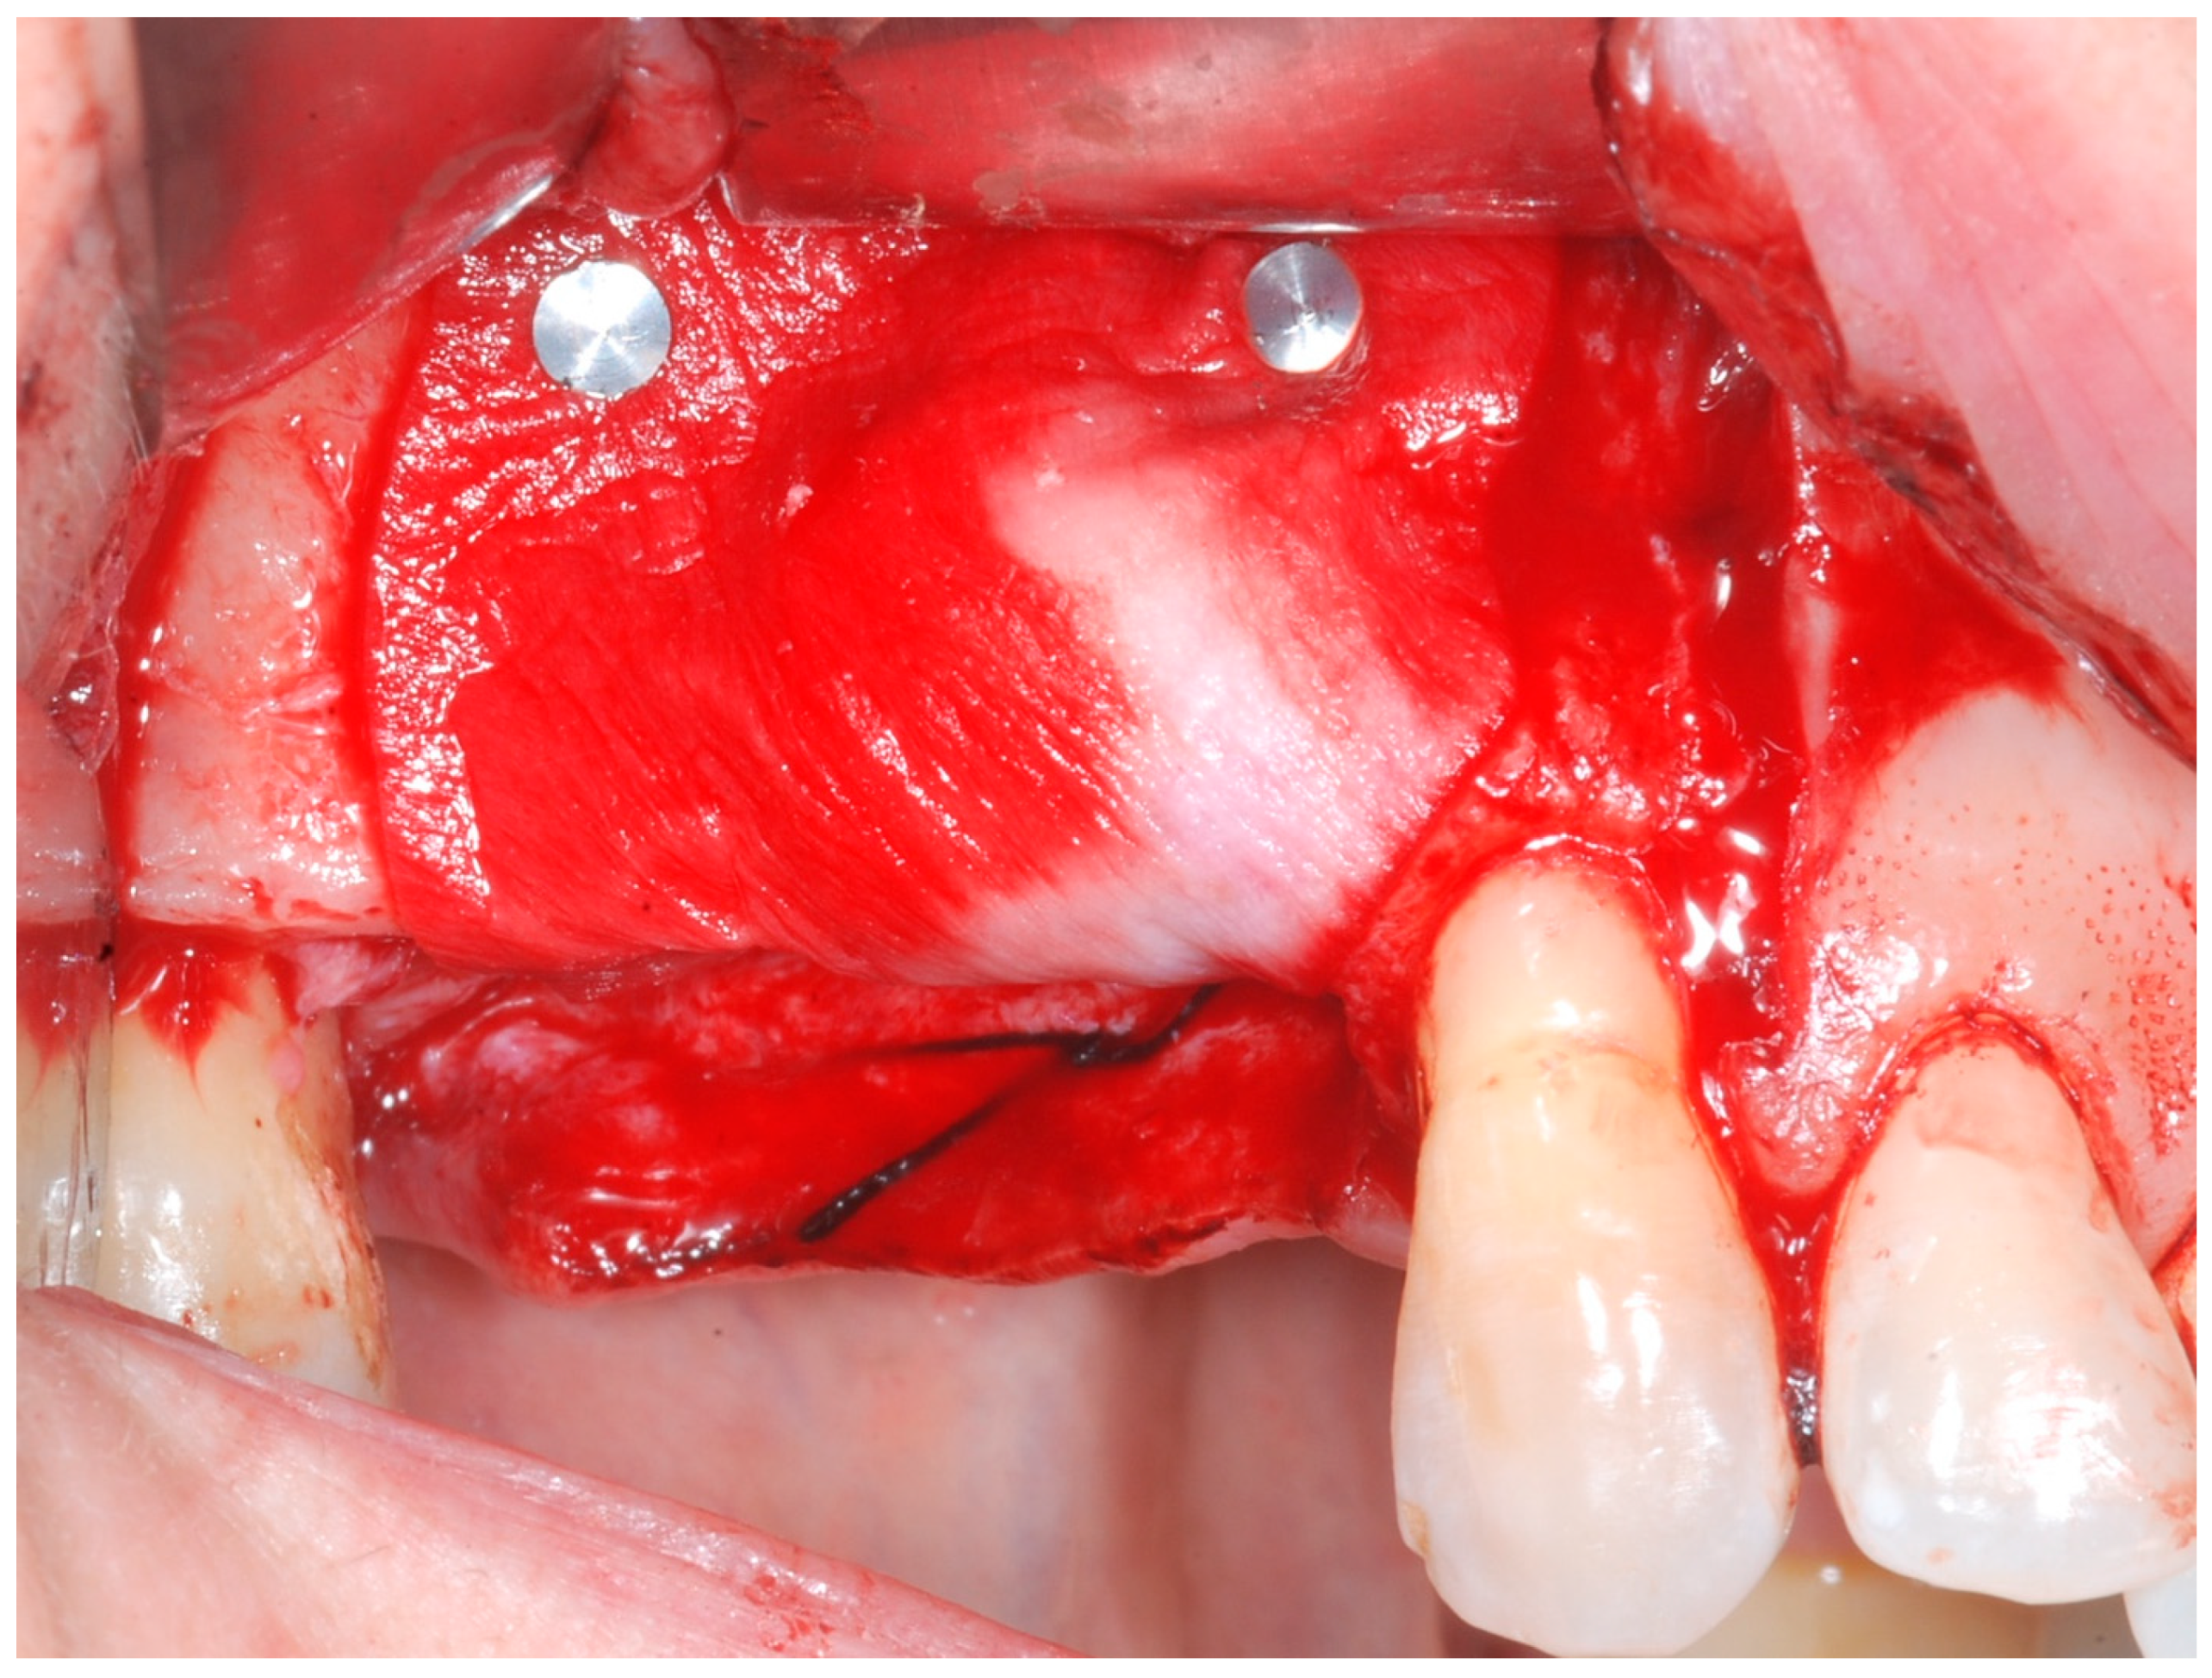

The cortical bone plate was perforated at numerous locations using a round bur in order to allow access of the cells from the bone and bone marrow to the area of regeneration. Subsequently, granules of cancellous deproteinized bovine bone mineral (DBBM) (Bio-Oss, Geistlich AG, Wolhusen, Switzerland), were placed in the defect area (Figure 5). A collagenous resorbable membrane (T-Gen, HYUNDAI BIOLAND Co., Ltd., 162, Gwahaksaneop 3-ro, Ochang-eup, Cheongwon-gu, Cheongju-si, Chungcheongbuk-do, 28125, Republic of Korea) was shaped and trimmed to cover the graft and to extend 2–3 mm onto the intact bony borders of the defect. The membrane was hydrated and the fixation was accomplished using fixation pins (MC Bio S.r.l., Como, Italy) (Figure 6).

Figure 6. CM fixated with titanium pins to cover the graft.